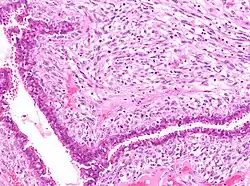

![]() |

Tuberculoid leprosy | Skin biopsy showing multiple peri-appendageal granulomas. | Category: Histopathology of leprosy | Leprosy |